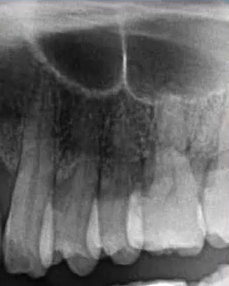

【病例5】

71岁,女性,右下颌后牙缺失要求种牙

曲断片:全面了解患者口腔情况

种植:缺牙位置、上颌窦、下颌神经管

牙周:牙槽骨、牙结石

牙体:龋坏、根尖炎、楔缺、合面磨耗

曲面断层片怎么看口腔精读 | 一次性教你看懂曲面断层片!_https://www.jmylbn.com_新闻资讯_第60张

上颌前牙区阴影:舌头位置不对→重拍?

下颌神经管显示不清:影响种植设计→进一步检查?

拍摄配合程度——年龄

初步诊断及预判:结合临床检查,哪些重点检查;影像经验,14、15,12、21,23,11、22

曲面断层片怎么看口腔精读 | 一次性教你看懂曲面断层片!_https://www.jmylbn.com_新闻资讯_第61张

曲面断层片怎么看口腔精读 | 一次性教你看懂曲面断层片!_https://www.jmylbn.com_新闻资讯_第62张

下颌种植主要判断:神经管走行及位置

左侧神经管下壁显示清晰,但上壁右侧神经管不清晰,前段疑似膨大。

曲面断层片怎么看口腔精读 | 一次性教你看懂曲面断层片!_https://www.jmylbn.com_新闻资讯_第63张

曲面断层片怎么看口腔精读 | 一次性教你看懂曲面断层片!_https://www.jmylbn.com_新闻资讯_第64张

局部小视野CBCT检查

曲面断层片怎么看口腔精读 | 一次性教你看懂曲面断层片!_https://www.jmylbn.com_新闻资讯_第65张

神经管位于46、47位置膨大,上壁不清。